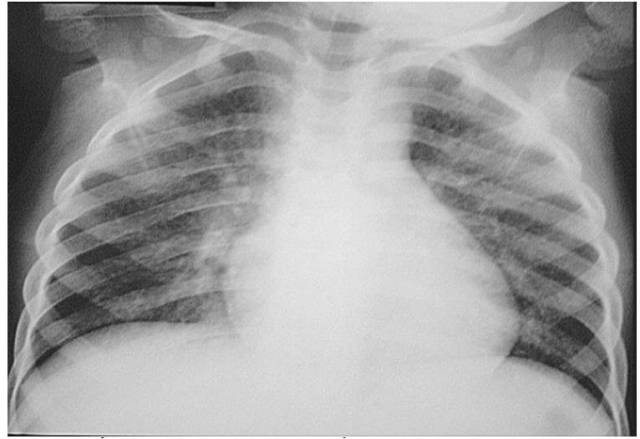

| Hình ảnh Xquang bệnh nhân bị viêm phổi sau khi sặc dầu hoả. |

Sau khi thăm khám và tiến hành các xét nghiệm cần thiết, các bác sĩ chẩn đoán trẻ bị viêm phế quản phổi sau uống dầu hỏa.